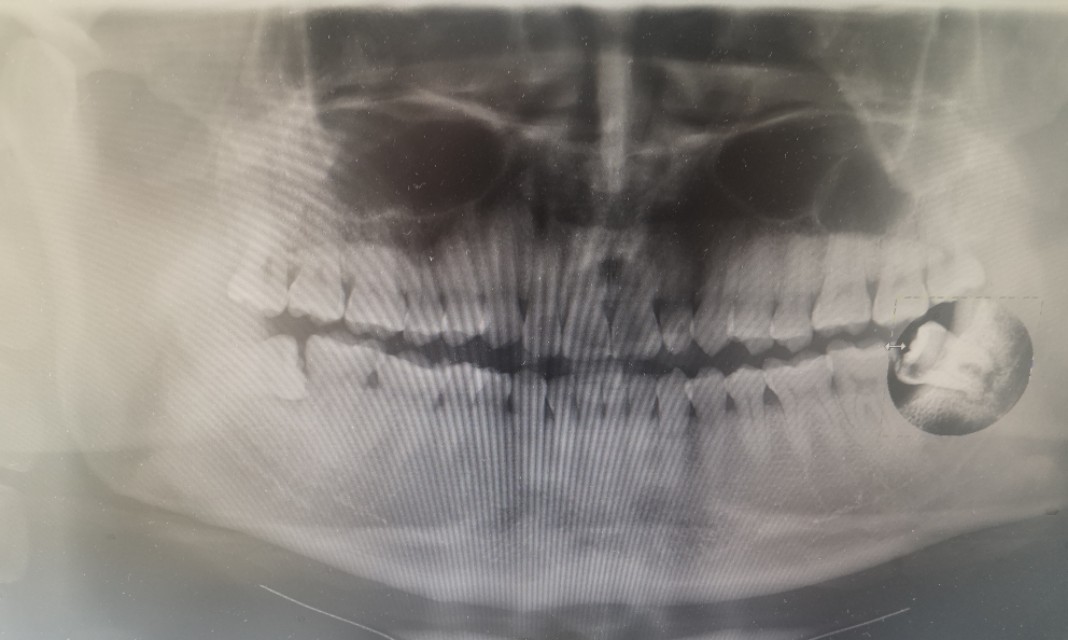

前两天疼痛见轻,但昨晚又开始难受,今天上午赶去医院,拍了个片。哎呀妈呀,有惊喜呀,实在是太惊喜了吧!

话说,我竟然有四颗智齿,上下左右各一颗,智齿啊智齿,你长得可真是全乎!我也是醉了醉了的!

下边两颗, 都是歪着长的,马上要顶到里边的大牙了,必须除之!

你丫作妖作怪,令我烦不胜烦,咋的,还有脸了?看在你长我嘴里这么多年的情分,本想给你拍个照留念的,但看了一眼,奈何你太磕碜,我瘆得慌,索性作罢,有拍的片子,就当你的遗照了吧!左智齿君,拜拜了您唻,再也不见,哈哈哈哈~